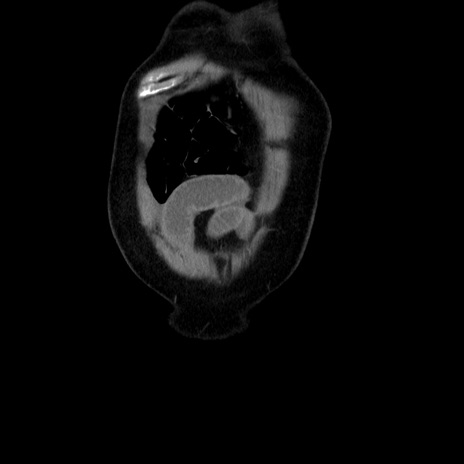

横断像

【症例】80歳代男性

【主訴】臍周囲痛

【現病歴】約6時間前から臍下部痛が出現。次第に腹部膨隆・背部痛も生じてきたため来院。背部痛の場所は変化しない。

【身体所見】意識清明、BT 36.3℃、BP  131/87mmHg、P 87bpm、SpO2 100%(RA)、臍周囲自発痛・圧痛あり、反跳痛なし、自発痛部位に一致して板状硬あり、腹部膨隆、腸雑音減弱、CVA tenderness両側陰性。

【データ】WBC 19600、CRP 0.33